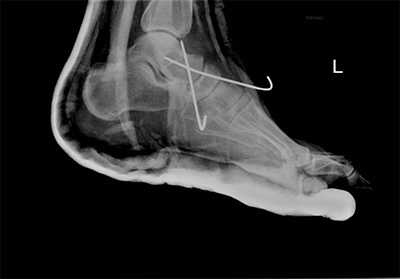

При смещении более 2 мм, нестабильности при функциональных тестах - рекомендовано открытое устранение вывиха с жёсткой фиксацией винтами или пластинами. Используются один или два продольных доступа в 1 и 2 межплюсневых промежутках. После обнажения первого предплюсне-плюсневого сустава первым этапом устраняется межклиновидная нестабильность, вторым этапом устраняется предплюсне-плюсневая нестабильность. В послеоперационном периоде сразу начинается разработка активного объёма движений. Нагрузку на стопу начинают постепенно, с тем чтобы полностью её восстановить к 6-8 неделе. Удаление спиц Киршнера производится через 6-8 недель, компрессирующих винтов через 3-6 месяцев. Возвращение к полной физической активности не ранее 9-12 месяцев после операции.

Открытое вправление вывиха, трансартикулярная фиксация 1-2-3 предплюсне-плюсневых суставов винтами.

В случаях этого повреждения показано оперативное лечение, открытое устранение подвывиха основания 2 плюсневой кости с фиксацией винтом. Устранение подвывиха производится из доступа в 1 межплюсневом промежутке, рубцовая ткань и остатки связки могут интерпонировать сустав, тогда потребуется их удалить. После вправления производится предварительная фиксация спицей и рентгенологический контроль.

Затем устанавливается винт соединяющий основание 2 плюсневой кости и медиальную клиновидную кость.

После осмотра в отделении ортопедии №2 ГКБ №13 принято решение о проведении операции - открытому устранению вывиха, артродезе 1-2-3 плюсне-клиновидных суставов, 1 межклиновидного сустава при помощи винтов и пластины, трансартикулярной фиксации спицами 4-5 плюсне-клиновидных суставов.

Первым этапом выполняется удаление костно-хрящевых экзостозов и рубцовых тканей из области всего сустава Лисфранка. После этого дистальный отдел стопы приобретает мобильность, достаточную для восстановления нормальной анатомии. Остатки суставного хряща полностью удаляются с 1-2-3 плюсне-клиновидных суставов, 1 межклиновидного сустава при помощи долота, осцилляторной пилы, кусачек Люэра, острой ложки Фолькмана. Для репозиции используются костные цапки.

Вершиной, ключом, блокирующим клином - в общем главной частью сустава Лисфранка является 2 плюсне-клиновидный сустав. По этой причине мы предпочитаем начинать фиксацию именно с него. Для артродеза используем винты с направленной в разные стороны резьбой FT Arthrex диаметром 4 мм. Они позволяют создать мощную межфрагментарную компрессию, а за счёт глубокой резьбы очень надёжно фиксируются в кости.

После восстановления 2 луча выполняем артродез межклиновидного сустава и 1 плюсне-клиновидного сустава. Учитывая что основная нагрузка ложится на 1 луч, дополнительно стабилизируем его при помощи пластины.